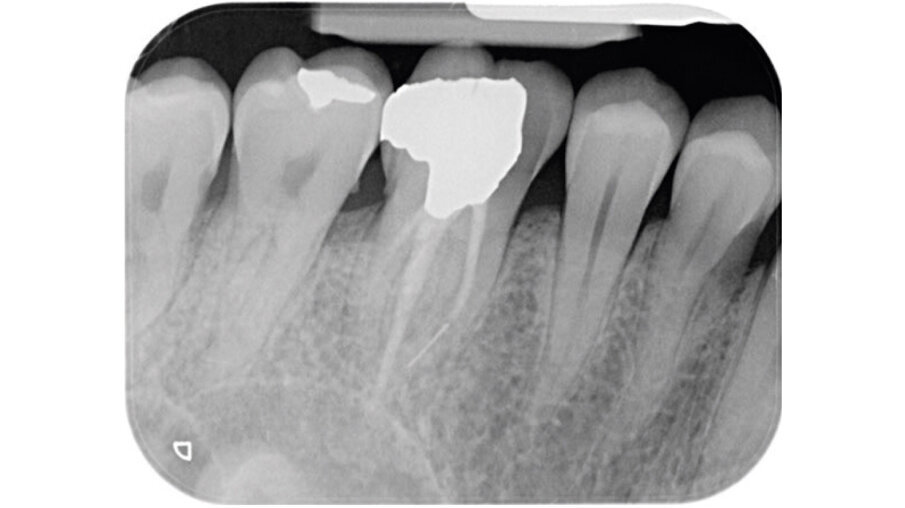

Un paziente maschio (ASA I), senza patologie croniche sistemiche e non fumatore, è stato sottoposto all’estrazione dell’elemento 16 a seguito del fallimento di terapie endodontiche e dell’impossibilità di eseguire un restauro coronale (Figg. 1a, 1b). Nella selezione del paziente sono stati criteri di esclusione: pregressa radioterapia nel distretto testa/collo, assunzione di farmaci che possano indurre ONJ, disordini ematici coagulativi, bruxismo, scarsa igiene orale domiciliare, occlusione instabile, carie non trattate, malattia parodontale non controllata, denti adiacenti a quelli da estrarre con mobilità di grado I o superiore, aspettative di risultato irreali, impossibilità o non propensi a tornare ai controlli di routine e di follow-up. La situazione dei tessuti è stata valutata pre-operatoriamente tramite radiografia periapicala (Fig. 1c) (VistaScan Mini Plus, Dürr Dental). Tramite la CBCT pre-operatoria è stato possibile fare una programmazione implantare. Sulla base dell’anatomia coronale è stata definita la posizione implantare (OnDemand3D, Cybermed), da questa analisi sono stati decisi anche il diametro e la lunghezza dell’impianto.

Fig. 1c_Foto iniziale, radiografia con cura canalare non ritrattabile, strumento rotto e probabile frattura verticale con sintomatologia da parte del paziente.